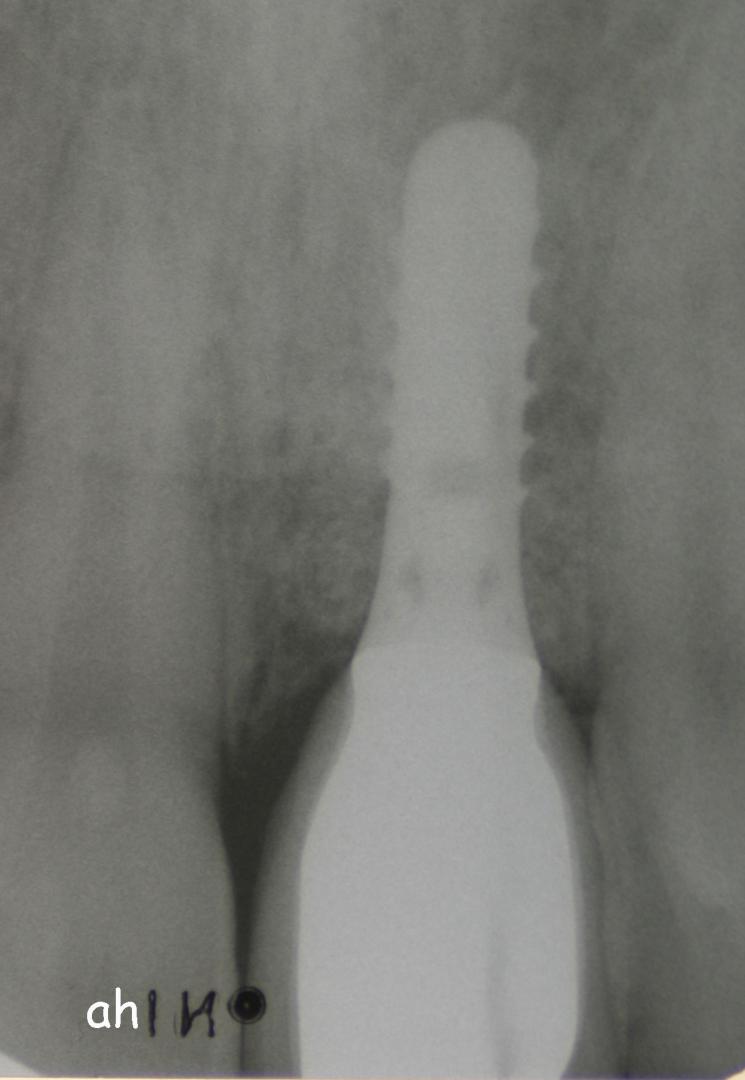

Exemple 1: Ce patient a perdu son incisive centrale gauche lors d'un accident. Un implant a été posé

Exemple 1: L'implant remplace la racine de la dent manquante

Exemple 1: L'implant s'est intégré dans l'os, une empreinte est effectuée. Le laboratoire peut réaliser la couronne en céramique.

Exemple 1: résultat final.